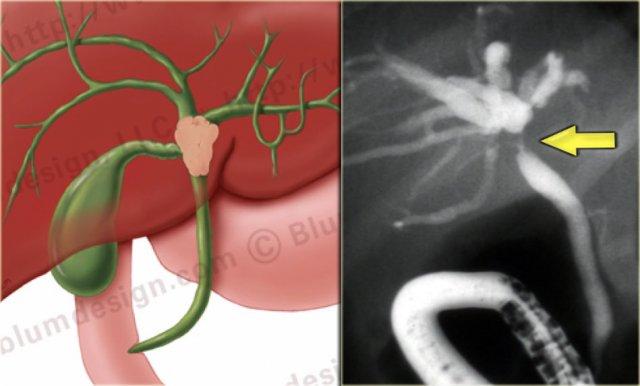

ERCP: Bệnh Caroli với giãn ống mật trong gan nặng. Không có tắc nghẽn. Giãn nhẹ ống mật chủ do viêm đường mật

Chụp đường mật đóng vai trò quan trọng trong quá trình đánh giá những bệnh nhân này, vì cần phải loại trừ tình trạng tắc nghẽn.

Điều này có thể được thực hiện bằng MRCP hoặc ERCP, như được minh họa bên trái.

Không có dấu hiệu tắc nghẽn.

Giãn nhẹ ống mật chủ là kết quả của viêm đường mật.

Có giãn khu trú xen kẽ với các đoạn hẹp của ống mật tại phân thùy IV (mũi tên).

Các ống mật còn lại và ống mật chủ bình thường.